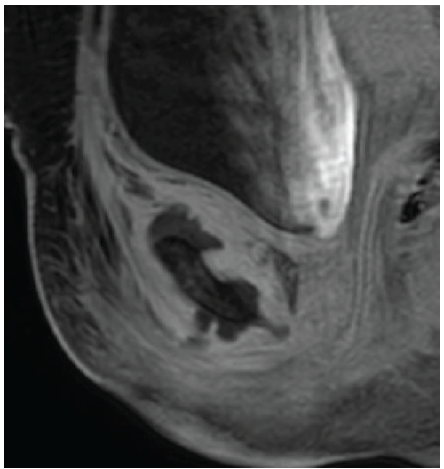

A 42-year-old South Asian woman with a history of hypothyroidism and recurrent UTIs presented with a 2-week history of lower abdominal pain radiating to both lower limbs, associated with high-grade intermittent fever. The pain was spontaneous in onset, progressive, and unrelated to trauma. She had previously received multiple short courses of antibiotics for recurrent UTIs. She presented to our center 10 days after the onset of symptoms. On evaluation, she was febrile (temperature 102°F), with suprapubic tenderness and restriction of active and passive hip movements bilaterally. Initial laboratory investigations revealed neutrophilic leukocytosis (total leukocyte count: 15,000/µL; neutrophils: 13,600/µL) and elevated C-reactive protein (195 mg/L). Urine routine examination demonstrated numerous red blood cells but no pyuria. A contrast-enhanced computed tomography renal stone survey showed perinephric stranding in the retropubic space suggestive of cystitis, with no evidence of collections, hematoma, or pelvic bone fractures. She was empirically started on intravenous piperacillin-tazobactam for presumed acute cystitis, given her history of recurrent UTIs. However, urine culture showed no growth after 48 h, while blood cultures grew MRSA. Antibiotics were escalated to intravenous teicoplanin (400 mg twice daily). Despite 48 h of appropriate therapy, she continued to have high-grade fever and worsening excruciating suprapubic pain radiating to the groin and medial thighs, severely limiting her mobility. Magnetic resonance imaging (MRI) of the pelvis with contrast revealed osteomyelitis of the bilateral pubic bones and superior pubic rami, with abscesses (10 mL and 1.5 mL) around the pubic symphysis, fluid collections in the right adductor and obturator externus muscles, and edema of the obturator internus, externus, and pectineus muscles (Figs. 1, 2, 3, 4).

Figure 2: Sagittal magnetic resonance imaging image demonstrating a well-defined collection in the superior aspect of the pubic symphysis (approximately 10 cc), suggestive of an abscess. The collection shows peripheral enhancement without extension into the abdominal cavity.

Figure 3: Sagittal magnetic resonance imaging showing a smaller abscess (~1.5 cc) in the inferior aspect of the pubic symphysis. Associated edematous changes are noted in the adductor muscle compartment, obturator externus, and pectineus muscles.